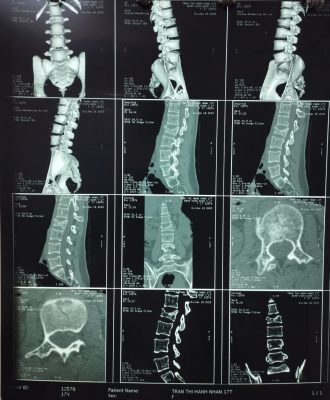

– Kết quả chụp phim chẩn đoán: chấn thương mất vững cột sống vỡ lún L2, có tổn thương thành sau thân đốt sống.

Phim CT Scan cột sống